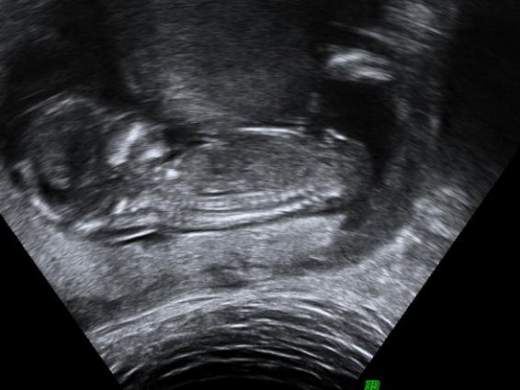

I just noticed this photo of what i think is the nub - can it really be one at this angle at 14 weeks and 2 days? xAttachment 8820

Im not sure and not an expert, but it does looks like to me a boy nub.

At 14 weeks, that looks like a penis and scrotum.

looks like a super boy nub to me... totally normal, too. I've seen other boy nubs like that. They rock because they are so obvious. I'd guess 90% that's a boy.

All boy! By 14 weeks it is actually looking like a penis and scrotum more than a nub :)